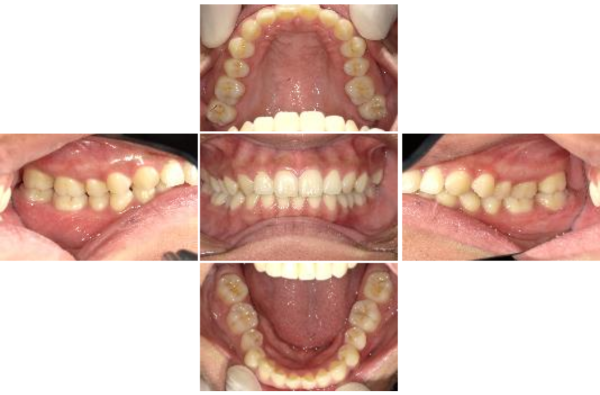

治療前

治療後

顎関節症(左側)口の開け閉めする際に痛い

顎関節症 左側臼歯関係 咬合関係が脆弱

行ったご提案・治療内容

対処療法ならスプリント療法。ただし、限界はある。もう一つは、噛み合わせ由来ゆえに、矯正での抜本療法としての対応。

患者は、最初はスプリント療法選択。物理的制約が落ち着いてから、抜本療法へ移行。矯正選択。

口がまっすぐ開けられるようになった。かつてあった首コリ、肩こり等気にならないレベルになった。体の重心のバランスが良くなった。